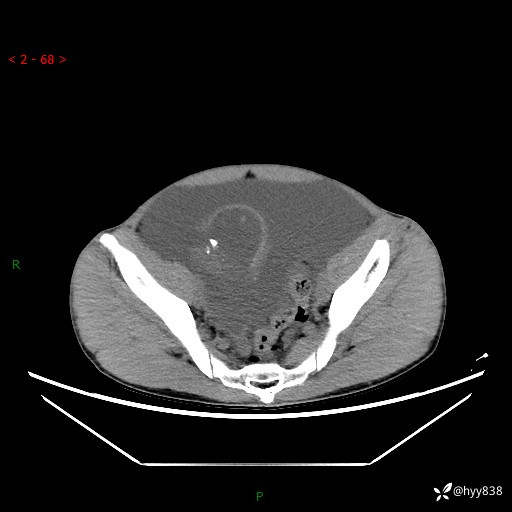

现病史:患者10天前无明显诱因出现腹部胀痛不适,无畏寒发热,无胸痛胸闷,无心慌气短,无恶心呕吐,无腹泻及黑便,无粘液血便及里急后重等症状,4天前在当地县人民医院就诊,行腹部CT示:下腹部占位性病变,腹腔及盆腔积液;今患者为求进一步诊治来我院治疗,门诊以“腹水”收治入院。 发病以来,精神饮食可,大小便正常,体重体力无明显变化。

腹部CT平扫+增强